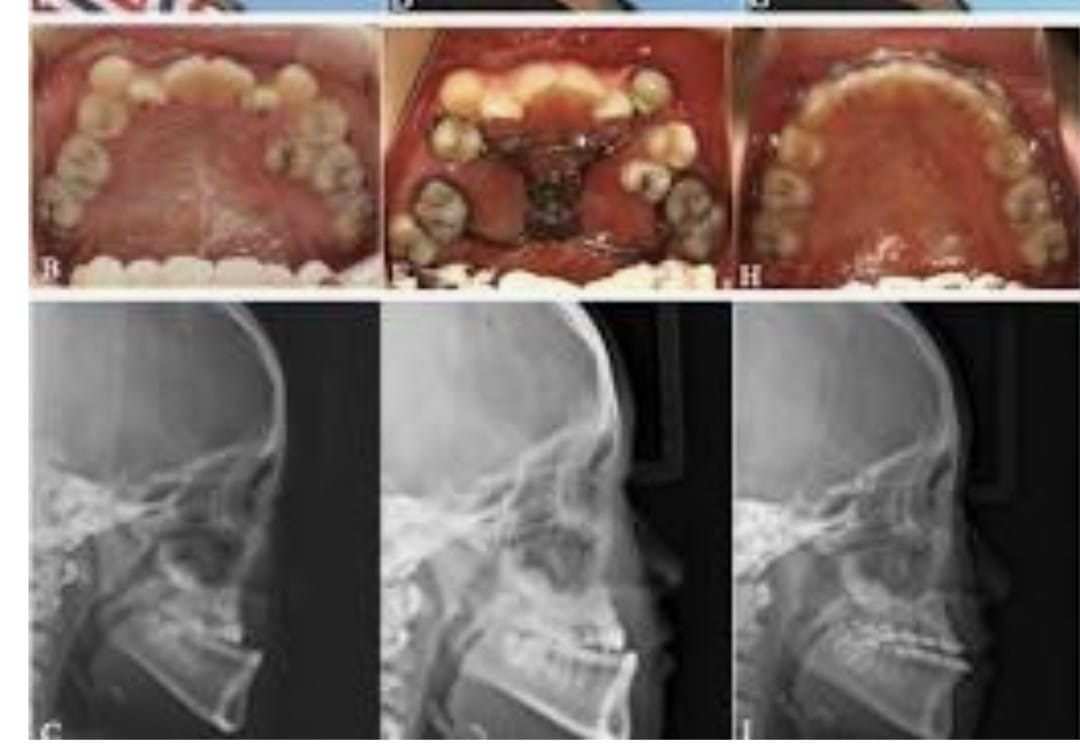

A deficient mandible refers to an underdeveloped or retruded lower jaw that can affect the balance and harmony of the facial profile. This condition may be present from birth or may develop due to growth abnormalities, trauma, or certain medical conditions. A recessed lower jaw can lead to functional concerns such as difficulty in chewing, speech issues, or improper bite alignment, in addition to affecting facial aesthetics.

Treatment for a deficient mandible focuses on restoring proper jaw position and improving overall facial balance. Depending on the severity, procedures may include jaw advancement surgery or other corrective surgical techniques designed to reposition and enhance the structure of the lower jaw. With careful evaluation and modern surgical methods, treatment helps improve both facial appearance and functional outcomes, providing long-term stability and enhanced confidence.

Pre-Surgical Preparation

- Pre-surgical Orthodontics: Often needed before the actual surgery takes place. Imaging: X-rays and CT scans are required.

- Planning: Virtual surgical planning is performed on a computer, along with model surgery.